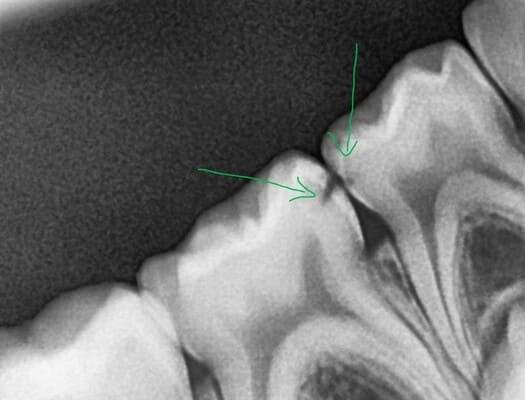

Не завжди маленька дірочка це про маленький карієс. Фісурний карієс досить часто розвивається вглиб і здатен вражати ще не достатньо мінералізовані зубні тканин юних пацієнтів. Зазвичай страждає жувальна поверхня, але інколи вражається і бічна поверхня, що має таку анатомічну структуру, як сліпа ямка. Даний пацієнт прийшов до нас саме з такою проблемою. Але завдяки своєчасному зверненню і гарній роботі нашої команди, ми змогли зупинити каріозний процес та відновити анатомію жувальної поверхні.

Карієс постійних зубів. Біленко Наталія.

У нашій клініці ми дбаємо не лише про здоров’я тимчасових зубів у малечі, а й активно займаємося лікуванням постійних зубів у підлітків — адже саме в цей період формується основа для майбутньої здорової усмішки. До нас звернувся юний пацієнт зі скаргами на застрягання їжі між нижніми жувальними зубами, що викликало дискомфорт під час прийому їжі. Після проведення рентгенологічного обстеження було виявлено контактний карієс, а також застарілу реставрацію на одному із зубів. Було проведено лікування карієсу та оновлення реставрації з урахуванням анатомії зубів. Усе відбулося комфортно для пацієнта — під місцевою анестезією та в спокійній атмосфері. У результаті відновлено правильний контакт між зубами, що повністю усунуло проблему та повернуло комфорт під час їжі.